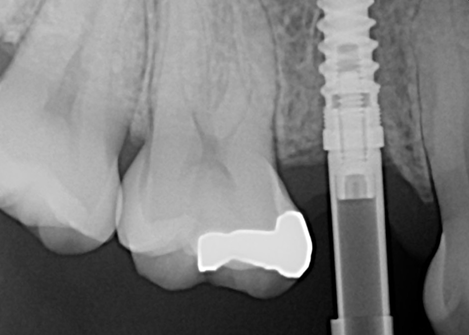

This comprehensive one-day course bridges the gap between implant placement and prosthetic restoration, focusing on the clinical and technical aspects of restoring dental implants in modern practice. Participants will gain practical knowledge in both analog and digital workflows, with emphasis on single-unit restorations while exploring multiple implant and full-arch rehabilitation protocols. The course includes a hands-on component where participants will practice digital scanning with an intraoral scanner and review the delivery considerations for screw-retained versus screw-mentable restorations.

Participants will learn to navigate the decision-making process between traditional and digital workflows, master impression techniques for various clinical scenarios, and understand the integration of CAD/CAM technology in implant dentistry.